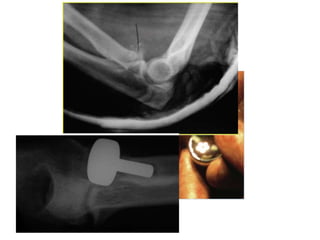

Radial head replacement

• Plane of radial head – 0.9 mm proximal to

lateral edge of coronoid

• Preop x- rays of opposite elbow

• Overstuffing – early joint degeneration

• Understuffing – Valgus instability

• Intraop – visible ulnohumeral gap – suggests

radial lengthening.

Radial head replacement •Plane of radial head – 0.9 mm proximal to lateral edge of coronoid • Preop x- rays of opposite elbow

Radial head replacement •Overstuffing – early joint degeneration • Understuffing – Valgus instability • Intraop – visible ulnohumeral gap – suggests radial lengthening.